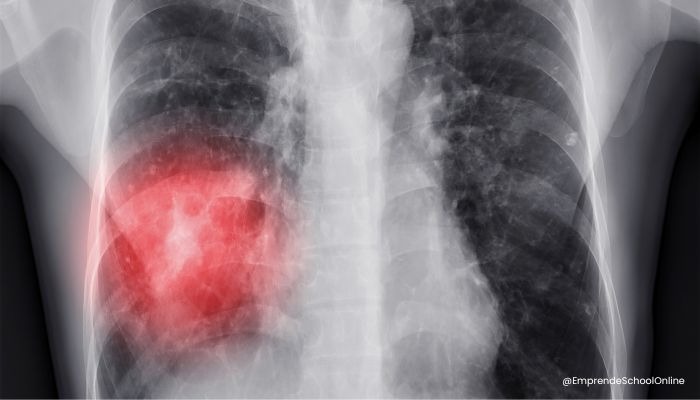

La inhalación frecuente de polvo de uñas puede desencadenar asma ocupacional. Los químicos en el polvo irritan las vías respiratorias, provocando dificultad para respirar, tos y fatiga.

Complementa con un colector de polvo profesional que elimine el polvo antes de que llegue a tus pulmones.

La exposición prolongada al polvo de uñas puede causar inflamación pulmonar conocida como neumonitis por hipersensibilidad. Esta condición es grave y puede llevar a dificultad respiratoria crónica.